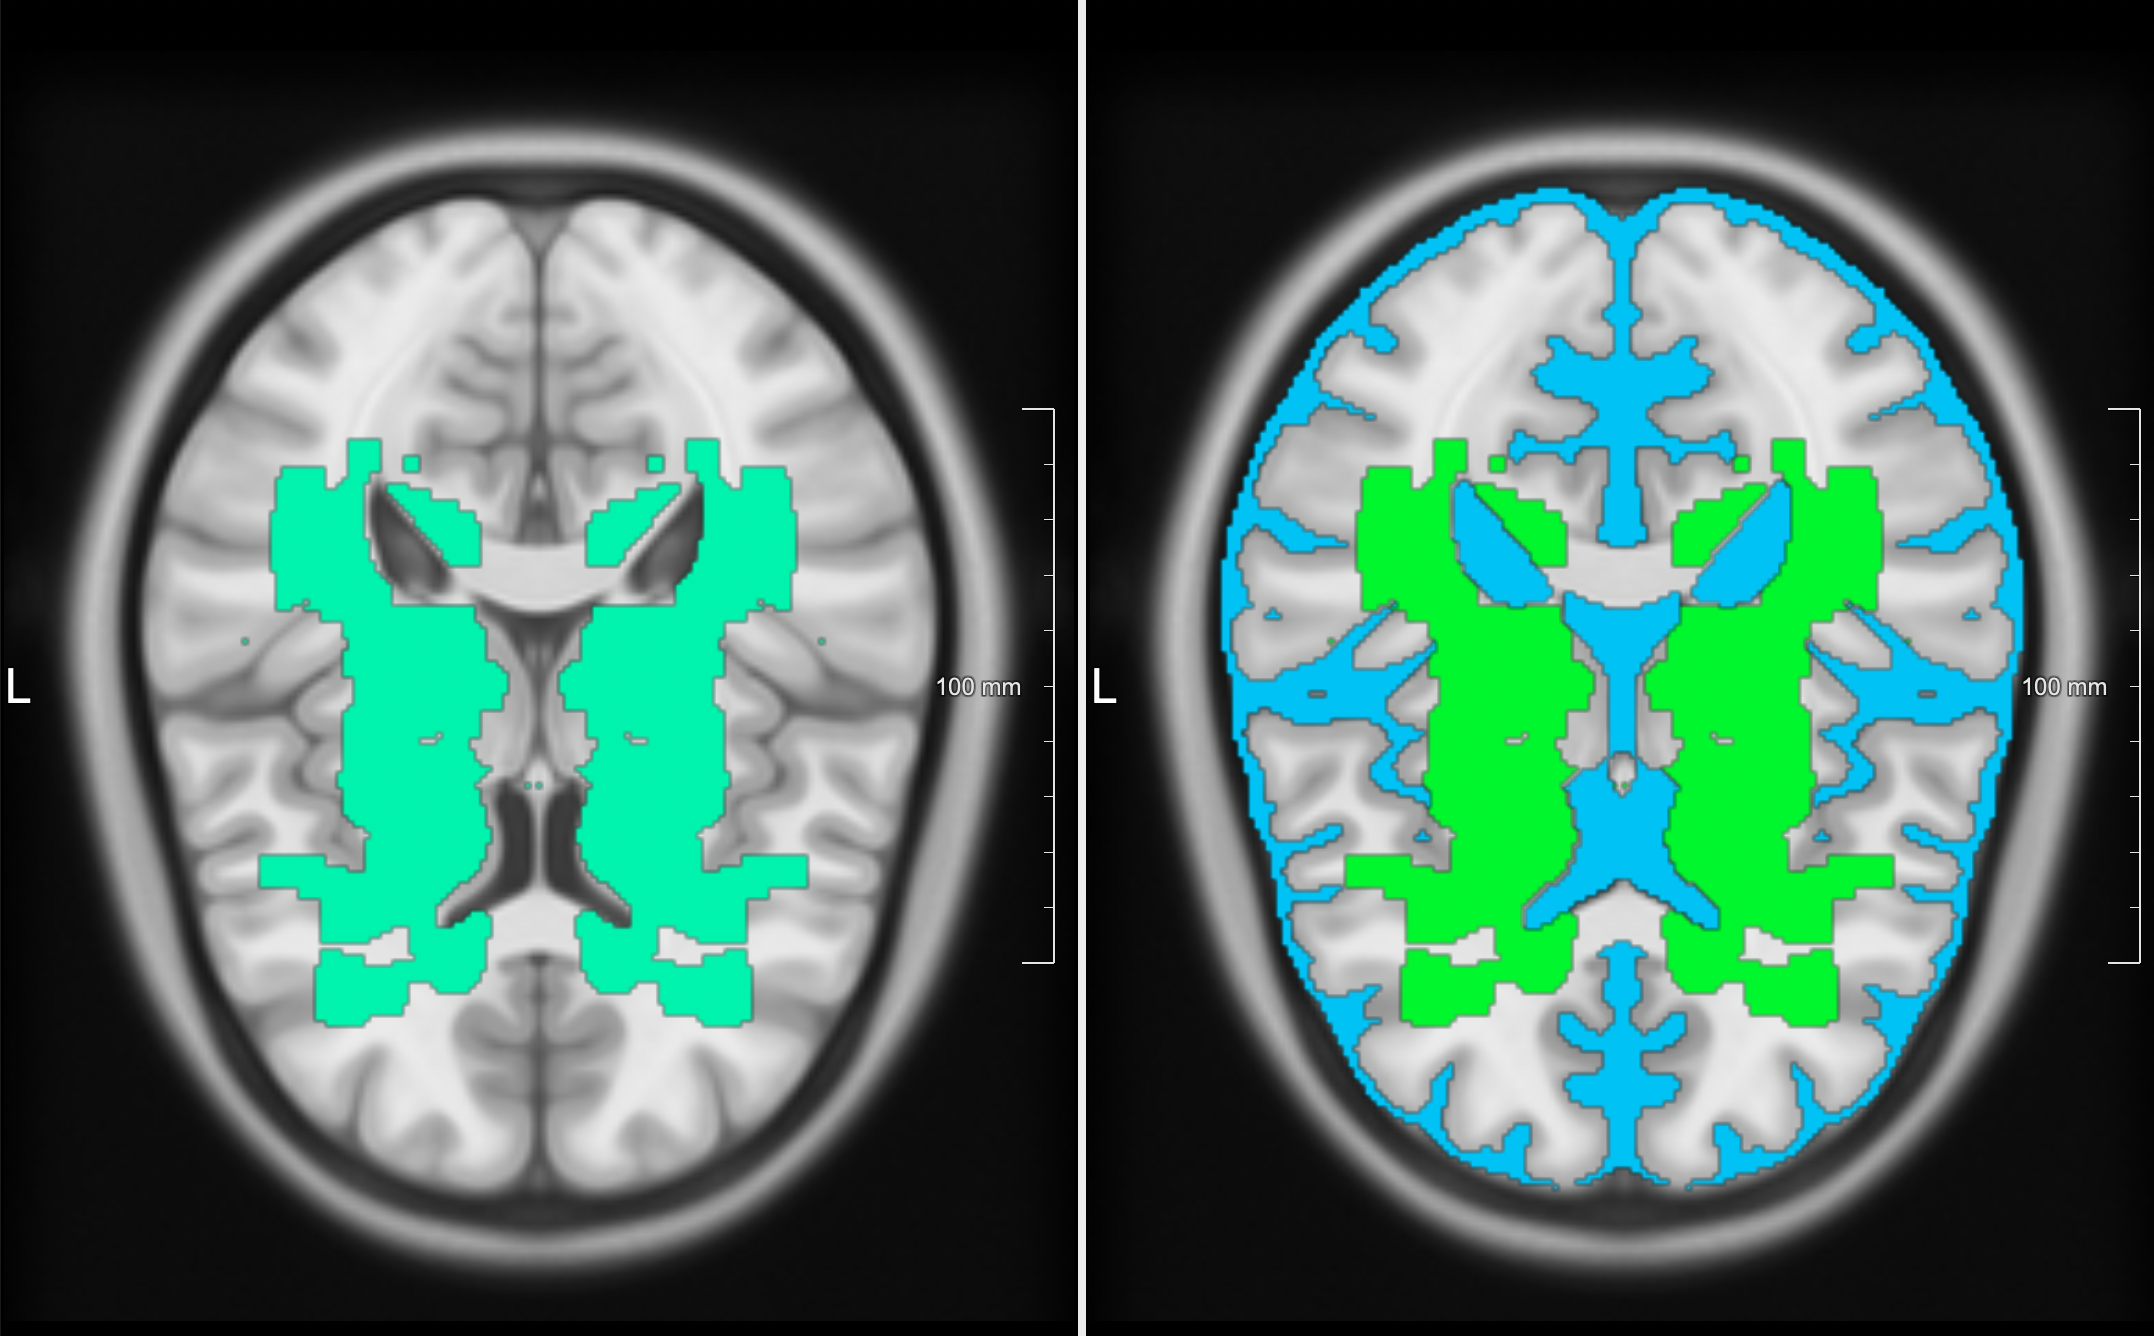

From the SMART-MR study [Biesbroek2013], we included 98 subjects for which manual segmentation of lacunes were available; and combined this with the 40 training subjects of the VALDO challenge. All images were registered to the MNI-152 [Fonov2011] atlas to create a lacune prevalence map. The resulting map (Figure 1) was made symmetric by mirroring, dilated by 7 mm in all directions, and the ventricles and CSF were removed.

Figure 1: The final lacune prevalence map in MNI152-space is shown on the left. Ventricles and extracerebral CSF were removed from the map with a CSF mask (light-blue on the right).